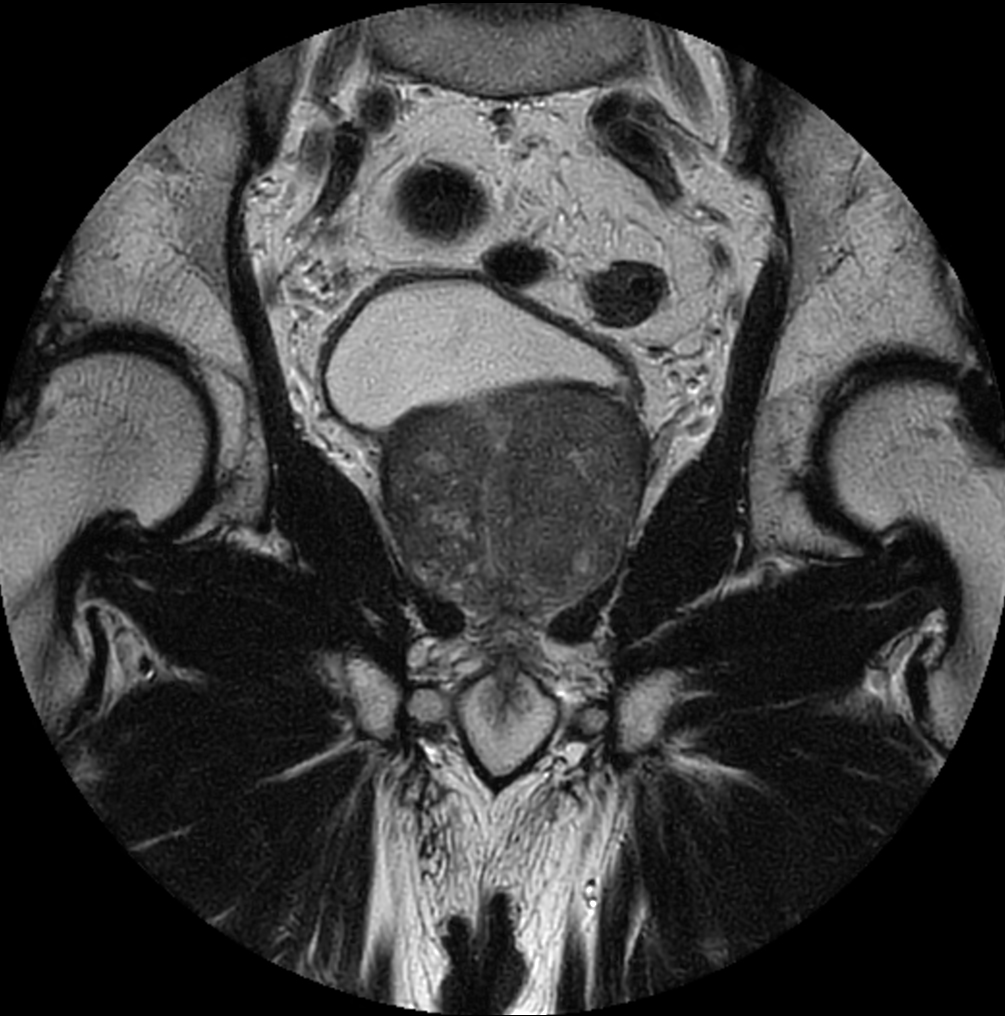

Coronal T2w TSE - MultiVane XD